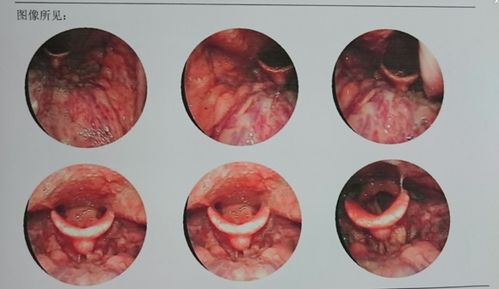

慢性咽炎是指咽部黏膜长期受到刺激,导致黏膜充血、水肿、分泌物增多等炎症反应,常见症状包括喉咙不适、异物感、咳嗽、声音嘶哑等,慢性咽炎的病因多样,包括吸烟、空气污染、胃食管反流、过敏、用嗓过度等。